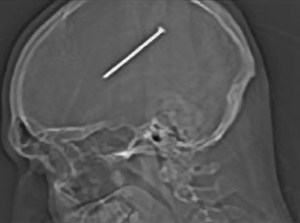

Dr. John Donne was watching the caretaker digging a grave in the churchyard, when the workman’s shovel accidentally threw up a skull. The Dr. took the skull in his hands to engage in serious meditation; and on looking at it, he found a headless nail sticking into the temple of the skull. The Dr. secretly drew it out, and wrapped into the corner of his handkerchief.